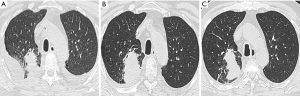

Chest CT interpretation

- Institutional cases: chest CT images of suspected PsP patients were independently appraised by two seasoned reviewers: an oncologist (M.X., 5-year experience in pulmonary imaging) and a pulmonary physician (Y.L., 2-year experience in pulmonary imaging diagnosis), using the Picture Archiving and Communication System (AGFA Healthcare, Mortsel, Belgium). All images were evaluated employing standardized lung window settings [width: 1,500 Hounsfield unit (HU); level: 2,500 HU]. In instances of discordance, a senior pulmonary radiologist (C.W., 18-year experience) and a pulmonary physician (L.P., 20-year experience) adjudicated the final PsP diagnosis. Additionally, immunotherapy efficacy was gauged by a radiologist (C.W.) and a pulmonologist (H.D.) in accordance with iRECIST criteria.

- Literature cases: Imaging data were extracted only if described in detail (e.g., lesion size changes, inflammatory features). Cases with ambiguous imaging reports were excluded (n=2).

Imaging findings and CT pattern development

The imaging results of the four patients with PsP are presented in Figures 2,3 and Figures S1,S2. Initial radiographic assessment revealed distinct PsP features: primary lesion enlargement (40.0%, 16/40), metastatic lesion progression (60.0%, 24/40), new pulmonary nodules (7.5%, 3/40), and lymph node enlargement (17.5%, 7/40). Notably, two cases (5.0%) demonstrated a paradoxical pattern of primary lesion growth accompanied by pleural effusion reduction—a characteristic yet underrecognized PsP signature.